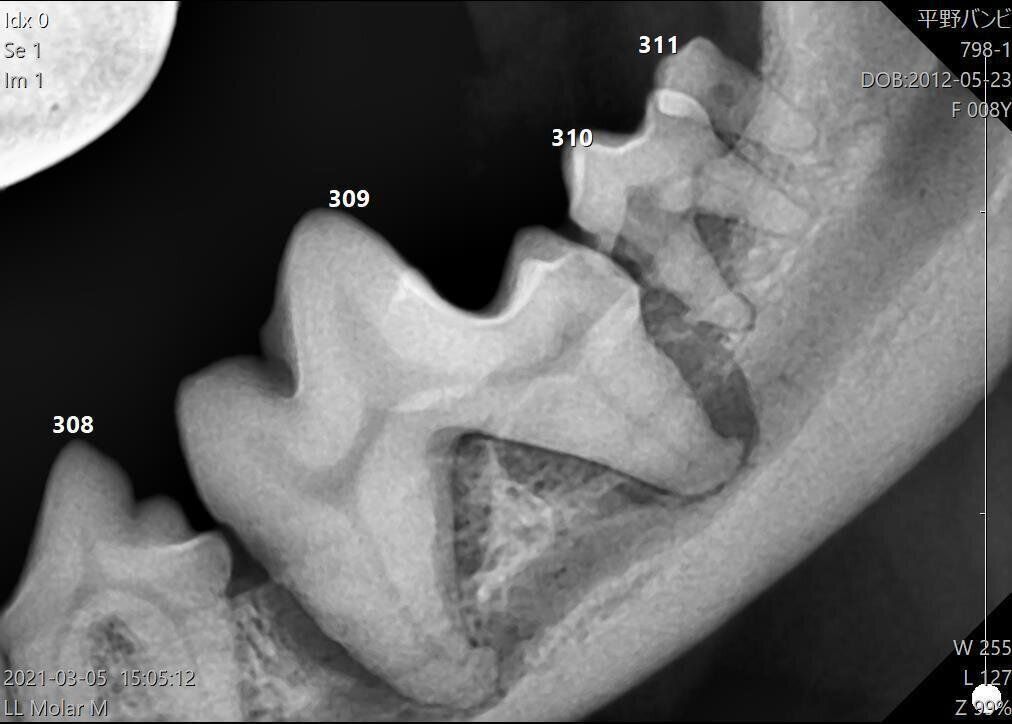

まずは、正常な状態の犬の歯のエックス線写真を見てみましょう。歯の根元部分に左右のあごの骨の付着部があります。

下あごを真下から撮ったエックス線写真

次に、歯周病が悪化してしまった犬の例を見て見ましょう。

前歯の骨が溶けて、下あごとの結合部分がなくなってしまっています。このように、歯周病が進んで歯の根元にまで炎症が広がると、歯を支える下あごの骨まで溶けて薄くもろくなってしまいます。すると、かたいものをあじる、あごをぶつけるなど、ちょっとした衝撃で骨が折れてしまうことも。もともとあごの骨が薄い小型犬はとくに注意が必要です。

骨が溶けて、左右のあごが皮一枚でつながっています